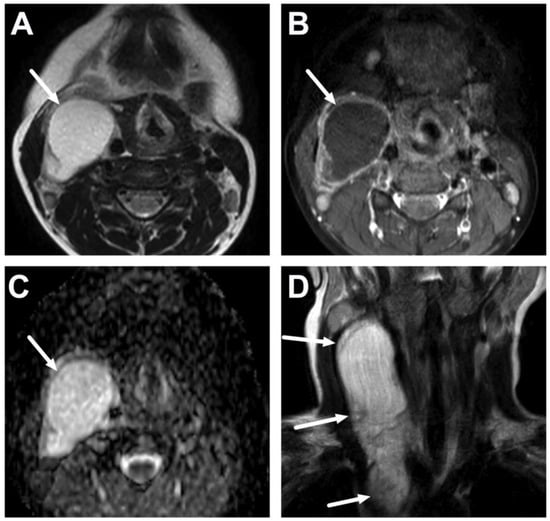

4.4. Sialadenitis